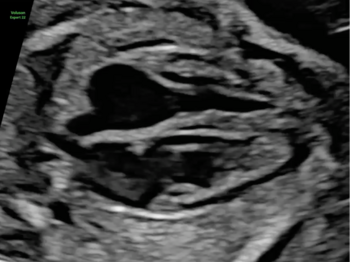

Zahlreiche kindliche Erkrankungen lassen sich mittels einer weiterführenden Feindiagnostik mit hochauflösenden Ultraschallgeräten frühzeitig erkennen. Idealerweise wird diese Untersuchung zwischen der 20. und der 22. Schwangerschaftswoche durchgeführt. Zu diesem Zeitpunkt ist die Entwicklung aller Organe bereits weitgehend abgeschlossen. In unserer Pränataldiagnostik und Schwangerenambulanz wird eine solche Untersuchung von speziell geschultem und erfahrenem Personal durchgeführt.

Im Rahmen der Diagnostik untersuchen wir die kindlichen Organe wie das Herz und die Nieren, aber auch andere Strukturen wie etwa das Gehirn oder Gesicht zum Ausschluss einer Lippen-Kiefer-Gaumenspalte. Auch die Wirbelsäule mit der Fragestellung nach einem offenen Rücken oder die Knochen werden beurteilt.

In unserer Frauenklinik am UKS wird nicht nur eine umfassende vorgeburtliche Diagnostik durchgeführt. Bestimmte Erkrankungen darunter eine kindliche Blutarmut aufgrund von Infektionen oder Blutgruppenunverträglichkeiten zwischen Mutter und Kind können wir bereits pränatal behandeln. In enger Kooperation mit den Kolleginnen und Kollegen der angrenzenden Fachgebiete wird der Patientin eine umfassende Beratung bei kindlichen Auffälligkeiten angeboten. So steht bei einer kindlichen Erkrankung oder Fehlbildungen nach der Geburt einer optimalen Versorgung nichts im Wege. So legen wir das Fundament für einen guten Start ins Leben.